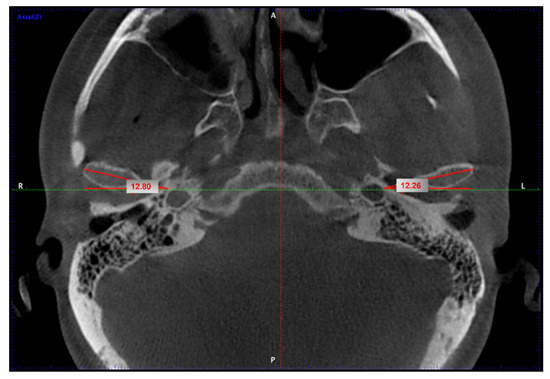

2. Materials and Methods